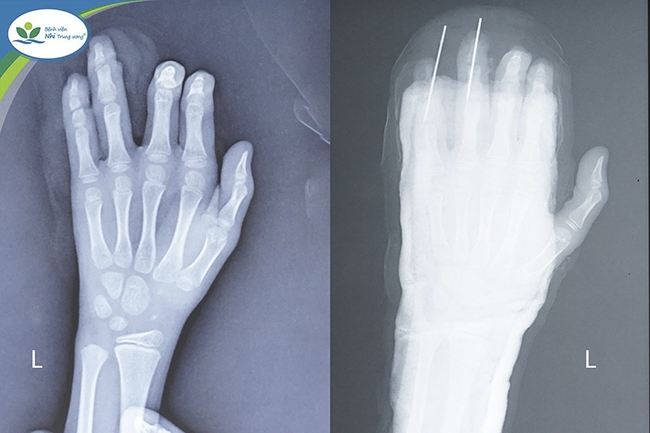

| Hình ảnh phim chụp X-Quang bàn tay của trẻ trước và sau phẫu thuật 3 ngày. |

Sau khi sơ cứu, bé được chuyển đến Bệnh viện Nhi Trung ương trong đêm để tiếp tục điều trị. Tại đây, bé nhập viện trong tình trạng ngón 4, 5 của bàn tay trái đã bị đứt gần rời, chỉ còn phần da dập nát ở ngón tay. Ngay lập tức, bé được các bác sĩ thăm khám, chụp X-Quang, làm xét nghiệm cần thiết và chỉ định phẫu thuật vi phẫu.

Bác sĩ Nguyễn Vũ Hoàng – Khoa Chỉnh hình, Bệnh viện Nhi Trung ương, người trực tiếp phẫu thuật cho bé trai cho biết: “Đây là một tổn thương rất nghiêm trọng, ngón tay 4, 5 bàn tay trái của trẻ đã đứt toàn bộ gân gấp, gân duỗi và một phần nguồn mạch nuôi, vết thương thấu khớp mẻ diện khớp và xương đốt ngón tay”.

Để phục hồi ngón tay cho cháu bé, các bác sĩ đã tiến hành lắp ráp xương, kết hợp xương bằng đinh Kirschner, nối lại gân duỗi và gân gấp ngón tay 4, 5 bàn tay trái, khâu phục hồi da ngón của bé. Ca phẫu thuật kéo gần 3 giờ đồng hồ đã cho kết quả thành công. Sau phẫu thuật các ngón tay đã hồng ấm, sức khỏe bệnh nhi tiến triển tốt. Tuy nhiên, để bàn tay có thể cử động như bình thường, bé vẫn cần một quá trình điều trị chống nhiễm trùng, bất động bột chờ lành thương và tập phục hồi chức năng.